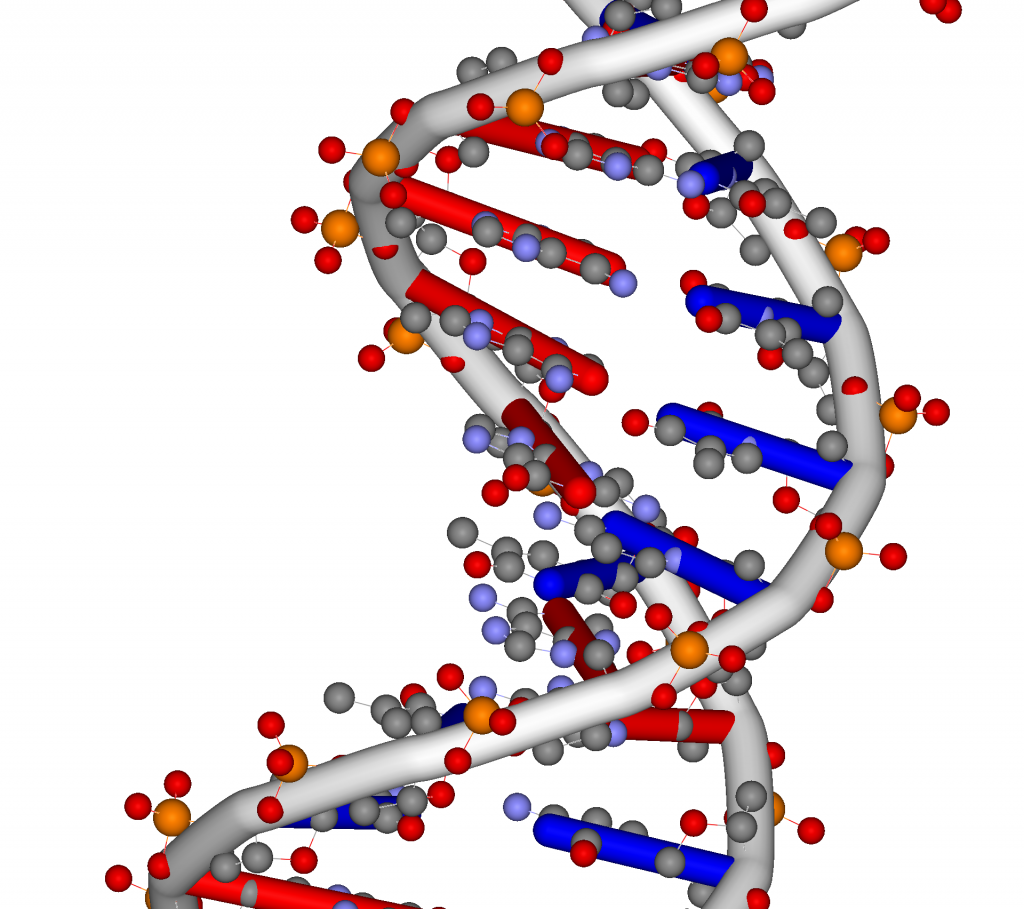

DNA

Mnohí ľudia sa domnievajú, že americký biológ James Watson a anglický fyzik Francis Crick objavili DNA v 50. rokoch 20. storočia, ale v skutočnosti ju prvýkrát identifikoval koncom 60. rokov 19. storočia švajčiarsky chemik Friedrich Miescher. V nasledujúcich desaťročiach po Miescherovom objave uskutočnili ďalší vedci množstvo výskumov, ktoré pomohli pochopiť, ako si organizmy odovzdávajú gény a ako sa riadi fungovanie buniek.